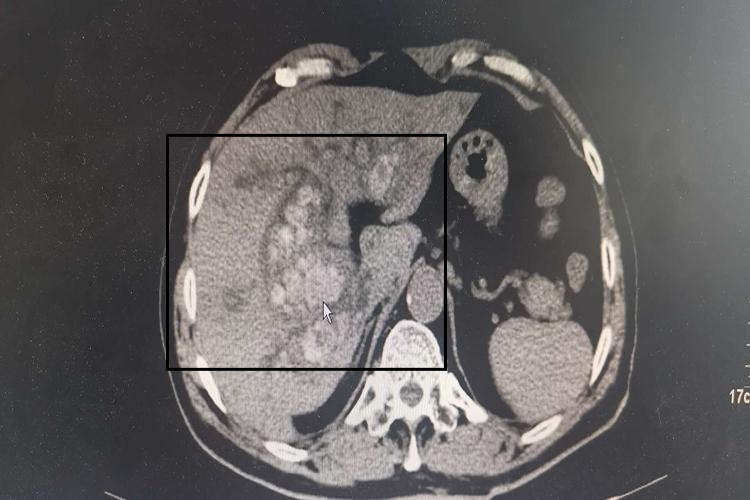

肝内低密度灶是指在肝脏影像学检查中,发现肝脏某一区域的密度低于周围正常肝组织的现象,通常是在CT或MRI等影像学检查中观察到的,表现为低信号或密度减低的影像。肝内低密度灶可能由多种原因引起。

- 肝癌:肝癌是一种恶性肿瘤,与肝炎、肝硬化、黄曲霉素等多种因素有关。在影像学检查中,肝癌可能表现为肝内低密度灶,但通常还需要结合其他检查手段进行确诊。

- 转移性肝癌:其他部位的恶性肿瘤可能转移到肝脏,形成转移性肝癌。这些转移性病灶在影像学检查中也可能表现为肝内低密度灶。

为了明确肝内低密度灶的具体性质,通常需要进一步进行CT造影增强扫描、病理检查等。对于良性病变,如肝囊肿、肝血管瘤等,若无症状或病灶较小,通常不需要治疗,定期观察即可。对于恶性病变,如肝癌等,则需要及时进行手术切除、化疗或放疗等综合治疗。